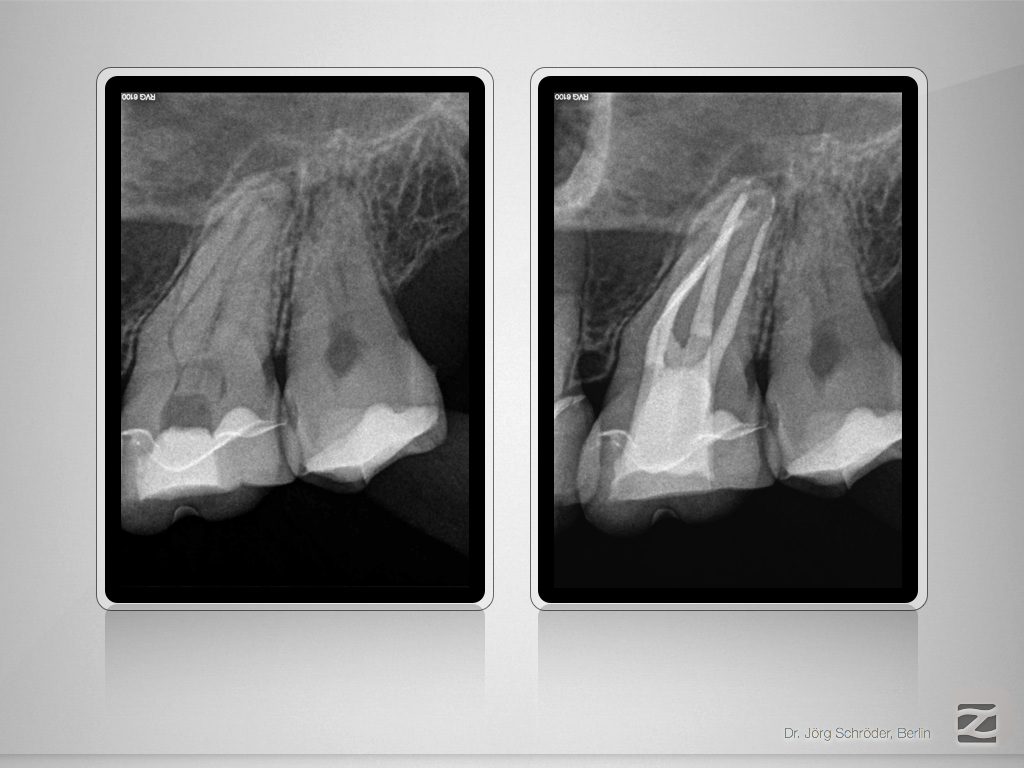

27D.010

Mutter aller Dentikel